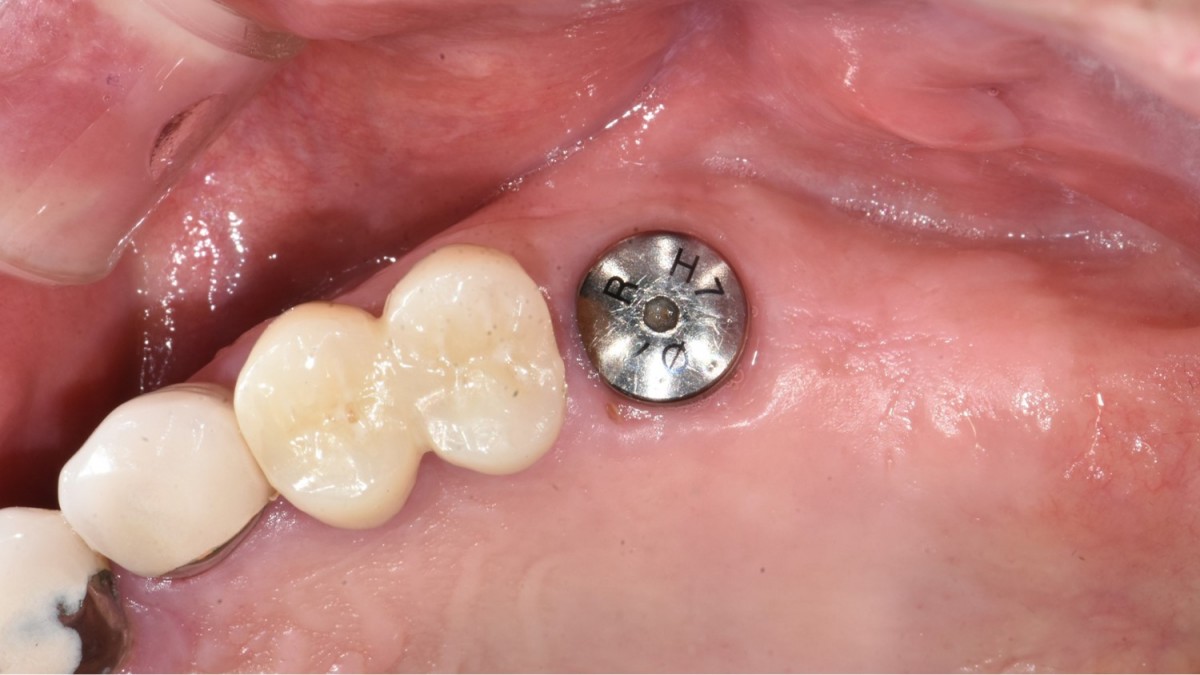

Immediate implant placement in the left molar of the maxilla.

A 57-year-old male patient recently underwent

implant restoration on the maxillary right molar. This time, he is scheduled to

proceed with the left molars. (ARUM implant system)

▲2 implants were placed. ArumDentistry NB1 5*10 (30Ncm) in the 1st molar and 5*10 (10Ncm) in the 2nd molar.